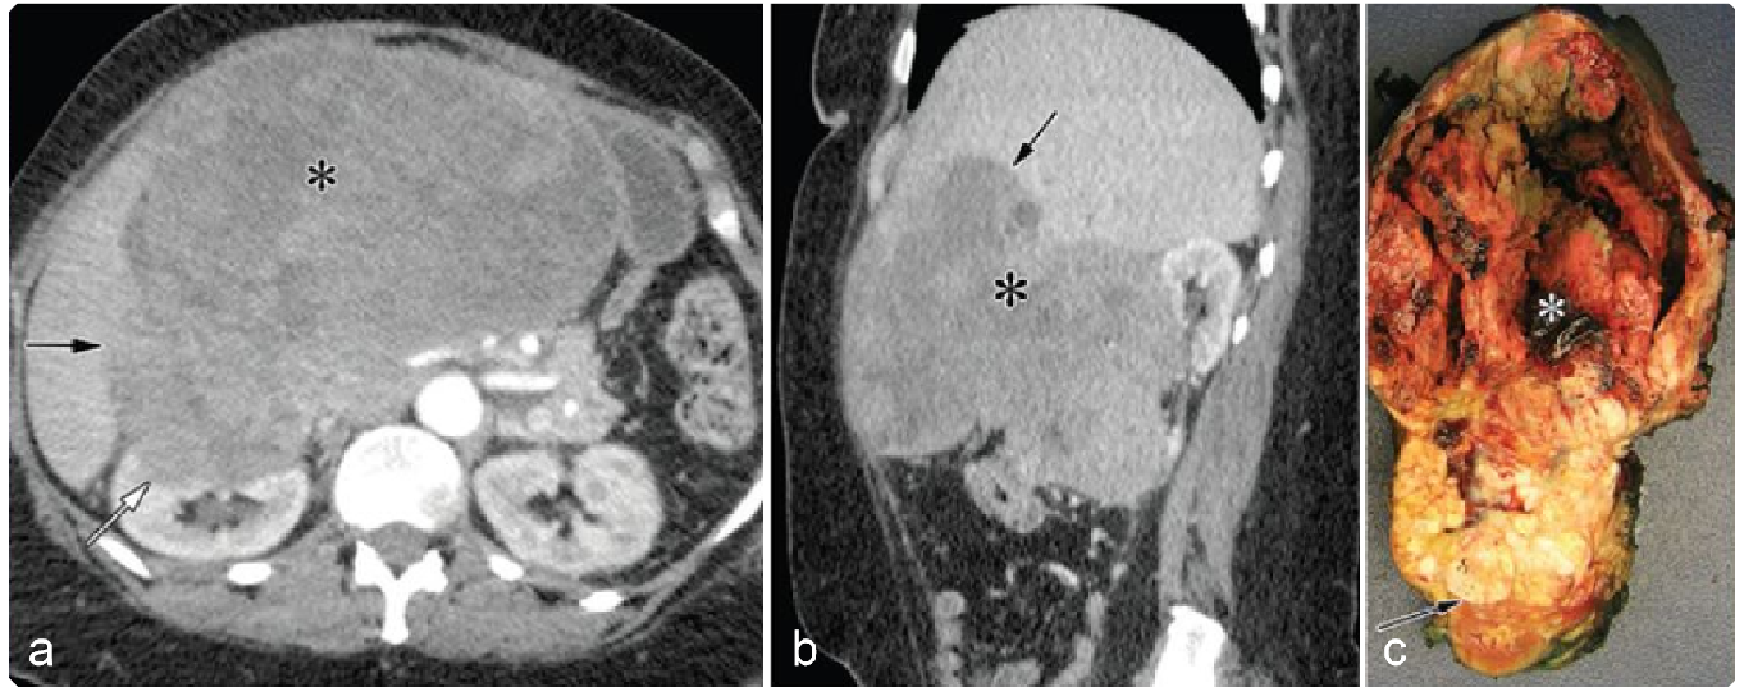

0a6556b925dbc726a8c295b13d4e5389.png 病例 9:腹膜后(血管外)平滑肌肉瘤  64岁女性右侧腹膜后巨大软组织肿块,不均质强化侵犯肝脏(黑箭)及右肾(白箭)。大体病理显示肿瘤侵犯右肾,瘤内出血、坏死(*)。

5cda817c00c60fa04c459763294e72d0.png 病例 10:腹膜后(血管外)平滑肌肉瘤  66岁男性,腹痛3个月,食欲下降,体重减轻右肾周巨大不均质肿块,内见坏死区,未见侵犯右肾。大体病理显示肿瘤位于右肾下部,完全位于肾外,肿瘤切面呈棕白色轮辐状外观。